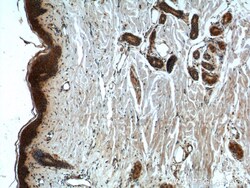

- Main image

- Experimental details

- Immunohistochemistry of paraffin-embedded human skin tissue slide using 21869-1-AP (CCHCR1 Antibody) at dilution of 1:50 (under 10x lens).